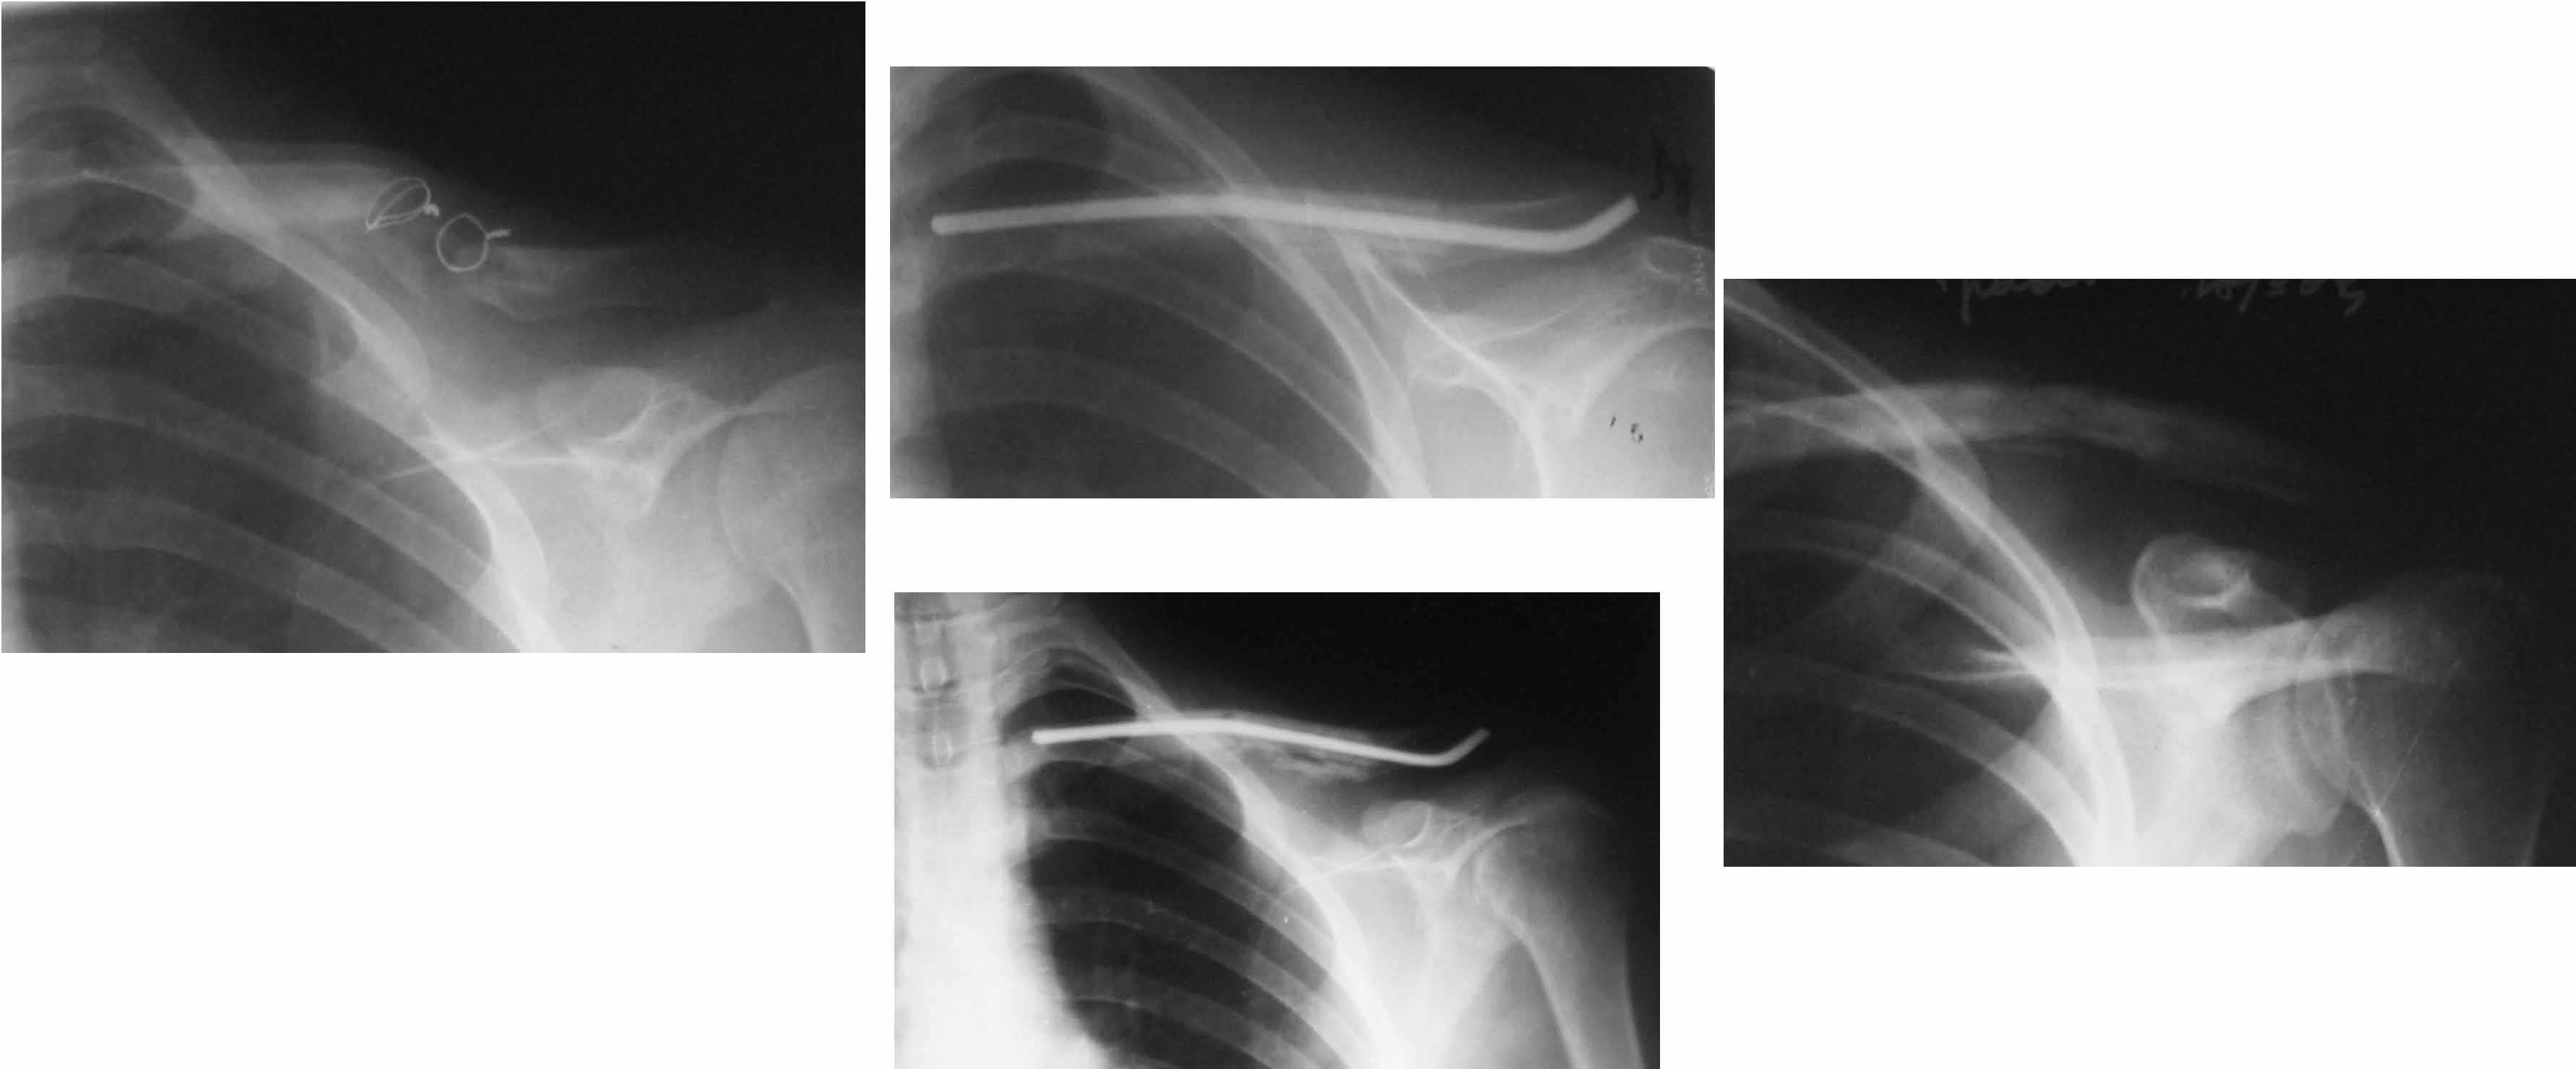

Уважаемые коллеги. Помогите с тактикой дольнейшего лечения несросшегося перелома ключицы. В отделение поступил больной, оперированный 2 мес. назад по поводу оскольчатого перелома средней трети правой ключицы. Перелом несросшийся, фиксатор несостоятелен, имеется смещение, угроза перфорации кожи. Рис. 1 Намми произведен реостеосинтез ключицы пластиной с угловой стабильностью, с замещением деффета диафиза ключицы костным аутотрансплантатом. Рис. 2 Через 5 мес. трансплантат рассосался, повторное смещение, несостоятельность импланта. Рис. 3Ваше мнение,что делать?

Идеальным вариантом представляется резекция ложного сустава, замещение образовашегося дефекта васкуляризированным малоберцовым трансплантатом и интрамедуллярный блокированный остеосинтез.

В условиях российской бедности мы делали свободным "столбиком" из малоберцовой и неблокированным штифтом. Результат был хороший (фото).